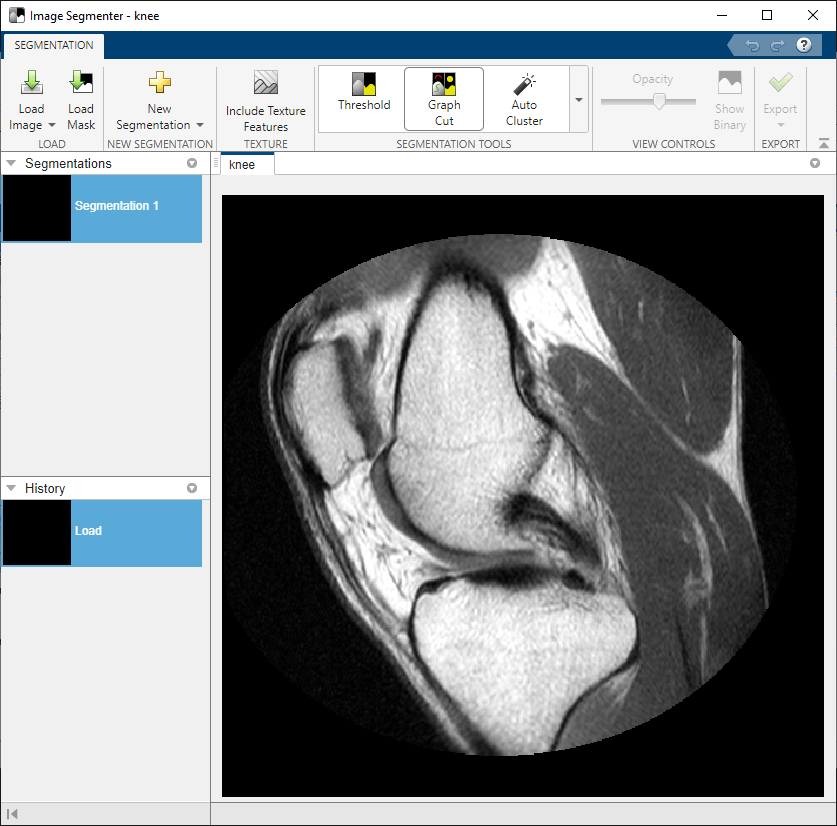

On the app toolstrip, click Load, and then select Load image from Workspace. In the Import from Workspace dialog box, select the image you read into the workspace. Image Segmenter displays the image you selected.

You can also open the image in the Image Segmenter app using the imageSegmenter command, as follows:

imageSegmenter(knee);